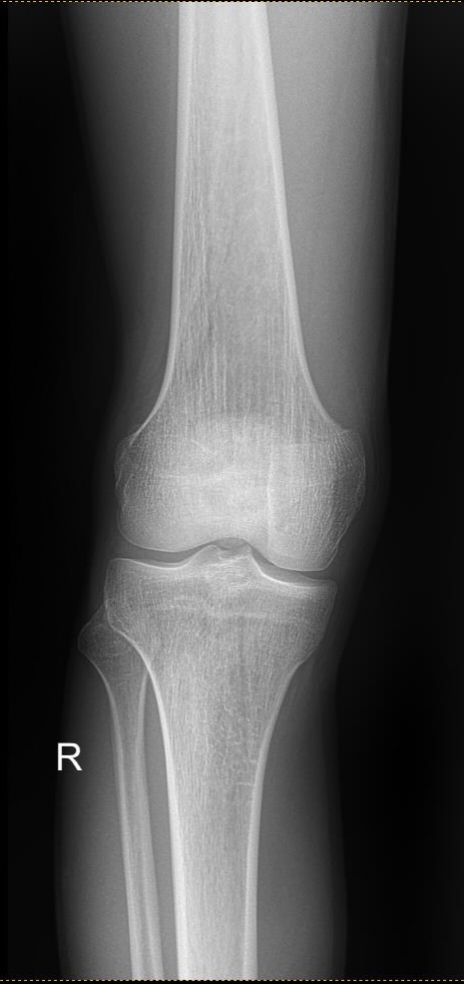

эксперты военно врачебной комиссии помогайте Аноним 16/10/25 Чтв 15:57:12 1645083 Ответ

в общем болит спина в районе поясницы при стоянии или ходьбе (где-то через 20-30 минут +-), началось в середине июля этого года после поднятия тяжести в саду. К врачам не обращался. Потом сходил в военкомат и получил б3. Понял что с такой проблемой мне в армии будет тяжко и погнал по неврологам. В общем вот пикрил мрт. Чё думаете? дадут хотя бы отсрочку на полгода на полечить?